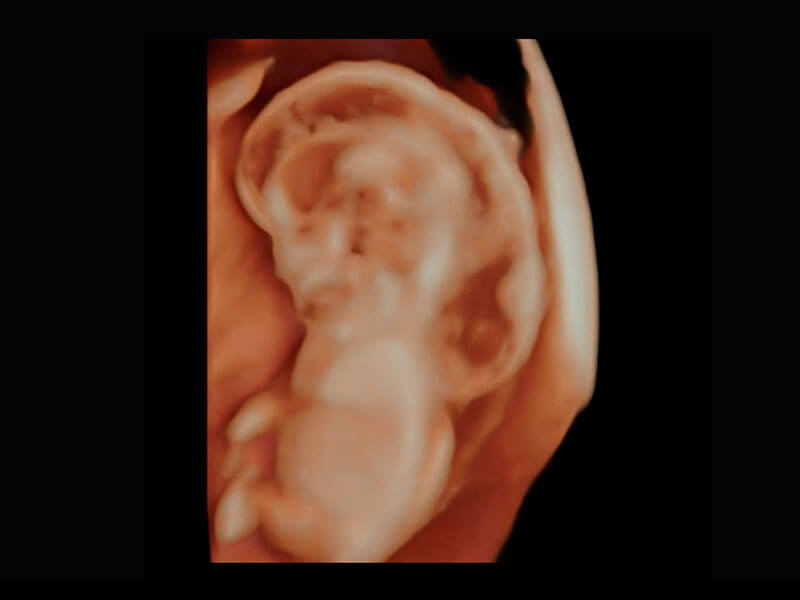

中晚孕筛查

P60提供简单易学易用的高端诊断工具,为您中晚孕筛查提供快速清晰的解剖信息。

S-Fetus能够助您在实时扫查过程中自动识别标准切面、自动测量并录入报告。一个按键,即可快速、高效地获取胎儿生理指标,简化您的产科检查操作。